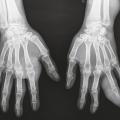

Goutte non commune

GOUTTE

TOPHUS

Image